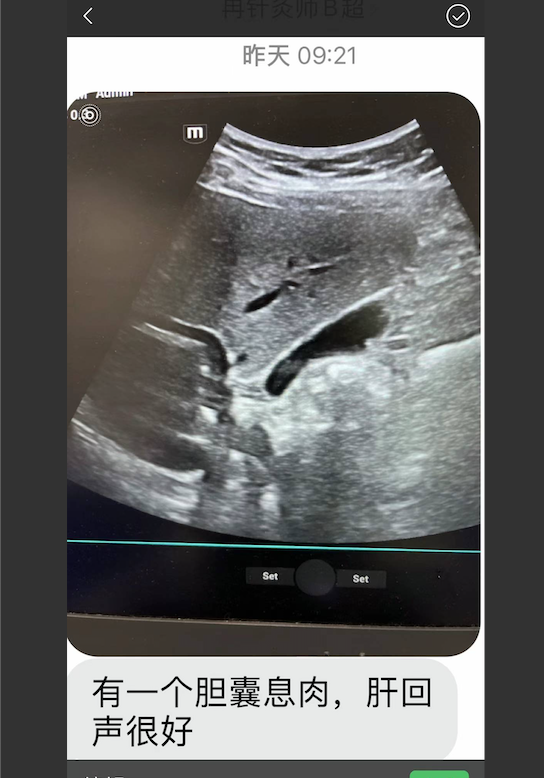

感谢张德超中医师治好了我的肝硬化。刚刚拍了一个片,结果出来说只看到有一个胆息肉,肝回声很好!!